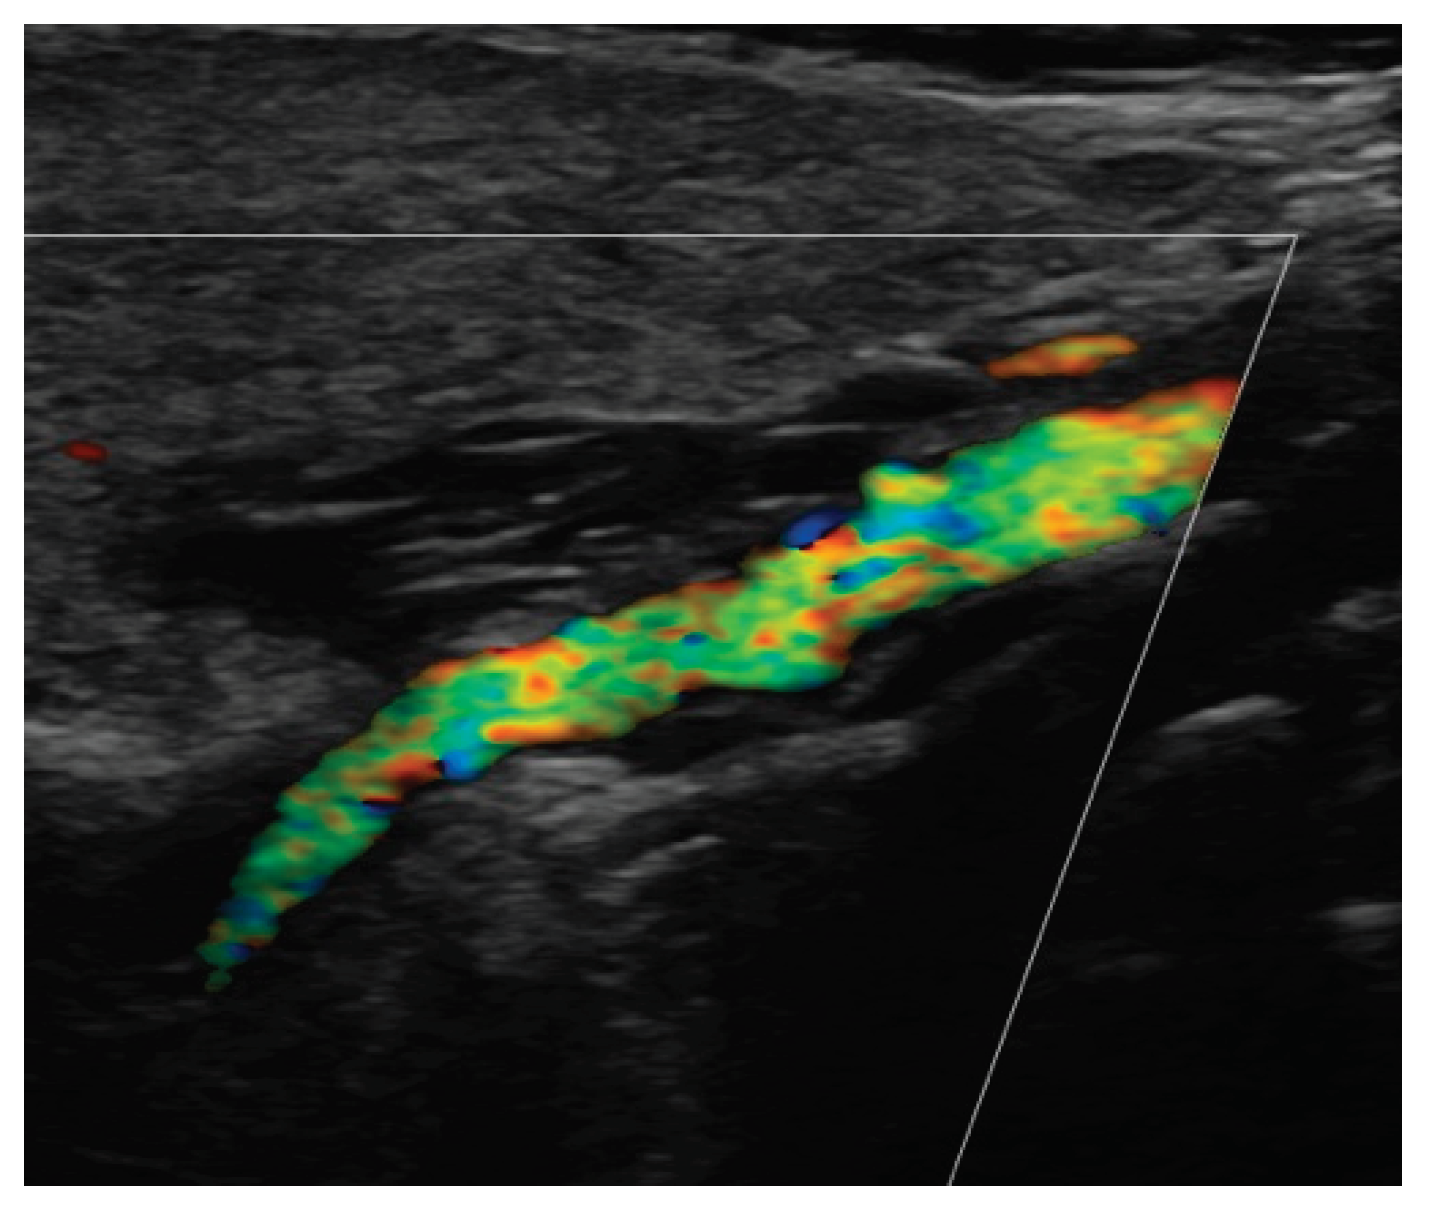

Since the advent of endovascular procedures, the histopathological classification has been replaced by an angiographic classification: focal or multifocal FMD. Multifocal FMD alternates areas of stenosis and dilation (“string of beads”) and is usually located in the mid and distal portion of the artery [147,148]. Recently, aneurysm, dissection, and arterial tortuosity have been included in the phenotype of FMD. However, a diagnosis of FAD cannot be established in the absence of focal or multifocal stenosis. Tortuosities can also be seen in the carotid, vertebral, and renal arteries. Tortuosity of the mid to distal portion of the internal carotid artery (ICA) may lead to an “S-curve”. The S curve is not specific for FMD, but its presence in individuals <70 years of age should alert the clinician [147]. Figure 1 and Figure 2.

Headaches are the most frequent, but non-specific symptoms (50-70% of patients with FMD) [147,151]. Pulsatile tintinnus may be associated with cervical artery dissection. The prevalence of cervical artery dissection and intracranial saccular aneurysm is higher among patients with FMD, with a higher rate of neurological complications (TIA, ischemic stroke, subarachnoid hemorrhage). Figure 3

The risk of long-term progression of FMD and the occurrence of aneurysm and dissection are not well-known [148]. CTA and MRA are the initial imaging modalities. Catheter-based angiography must be reserved for cases that may require intervention. Carotid DUS maybe useful for surveillance, but with some drawbacks: unsatisfactory access to vertebral and carotid arteries (especially the distal cervical portion of the ICA and intracranial arteries), no validated criteria for FMD [147]. Figure 4 and Figure 5